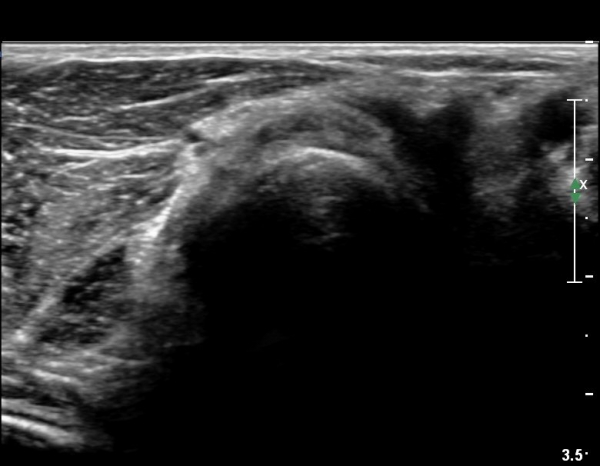

¿Ü»ó°ú¿¡¼­ ¼Õ¸ñ ½ÅÀü°Ç ´ÜµÎ Á¾´Ü¸é°Ë»ç¿¡¼­ ƯÀÌ ¼Ò°ßÀ» º¸ÀÌÁö ¾Ê´Â´Ù(»çÁø 1, 2)